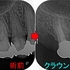

分割確認のレントゲン

ヘミセクション後 フルジルコニアクラウンを入れさせてもらったのですが・・・

2026 EEdental SSY (3).jpg

クラウンを入れて2年半後にコアごとクラウン脱離

骨の所見を見ると、咬む力による問題+クラウンに強すぎる材料を使ってしまったここと推測

患者さんに謝り、もう一度根管治療からやり直させてもらいました。

ヘミセクションの際に自分がレジンコア作るべきだったと反省。。。

仮歯を入れて経過を見て行き

ようやく1年、骨もしっかり戻ってきてくれています。

この後、クラウンは弱目の材料で作っていこうと計画しています。